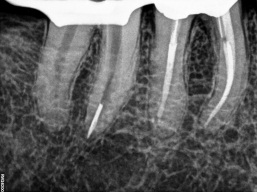

O instrumento Ultrassônico específico escolhido deve ter um comprimento que alcance a obstrução e um diâmetro pequeno o bastante para fornecer visão direta no instrumento fraturado. Esta ponta de inserção é colocada contra a cabeça do seguimento fraturado no interior do canal, ativada e movida na direção anti-horária em torno da obstrução. Esse trabalho ultra-sônico utiliza o Stropko Irrigador (stropko.com) com uma cânula luer-lock de 29 ga(Ultradent Producs) para fornecer uma corrente contolada de ar, que serve para soprar a apoeira dentinária e manter a visão contínua.

O objetivo deste método ultra-sônico é trefinar, lixar a dentina e expor 2 a 3 mm do aspecto mais coronário da obstrução, ou cerca de um terço de seu comprimento total. Algumas gotas de uma solução de 17% de EDTA são pingadas no canal e servem como um adjuvante de remoção potente ao colocar uma ponta energizada contra a cabeça de um segmento de lima quebrado. Clinicamente, depois de criar uma plataforma de preparo e expor a cabeça de um segmento de lima quebrado, colocar gentilmente a ponta energizada entre a lima afunilada e a parede do canal afunilado muitas vezes faz com que o instrumento quebrado se solte, desenrosque e saia do canal. No entanto, procedimentos ultra-sônicos podem não ser bem-sucedidos e, nesses casos, um método de remoção secundária será necessário.